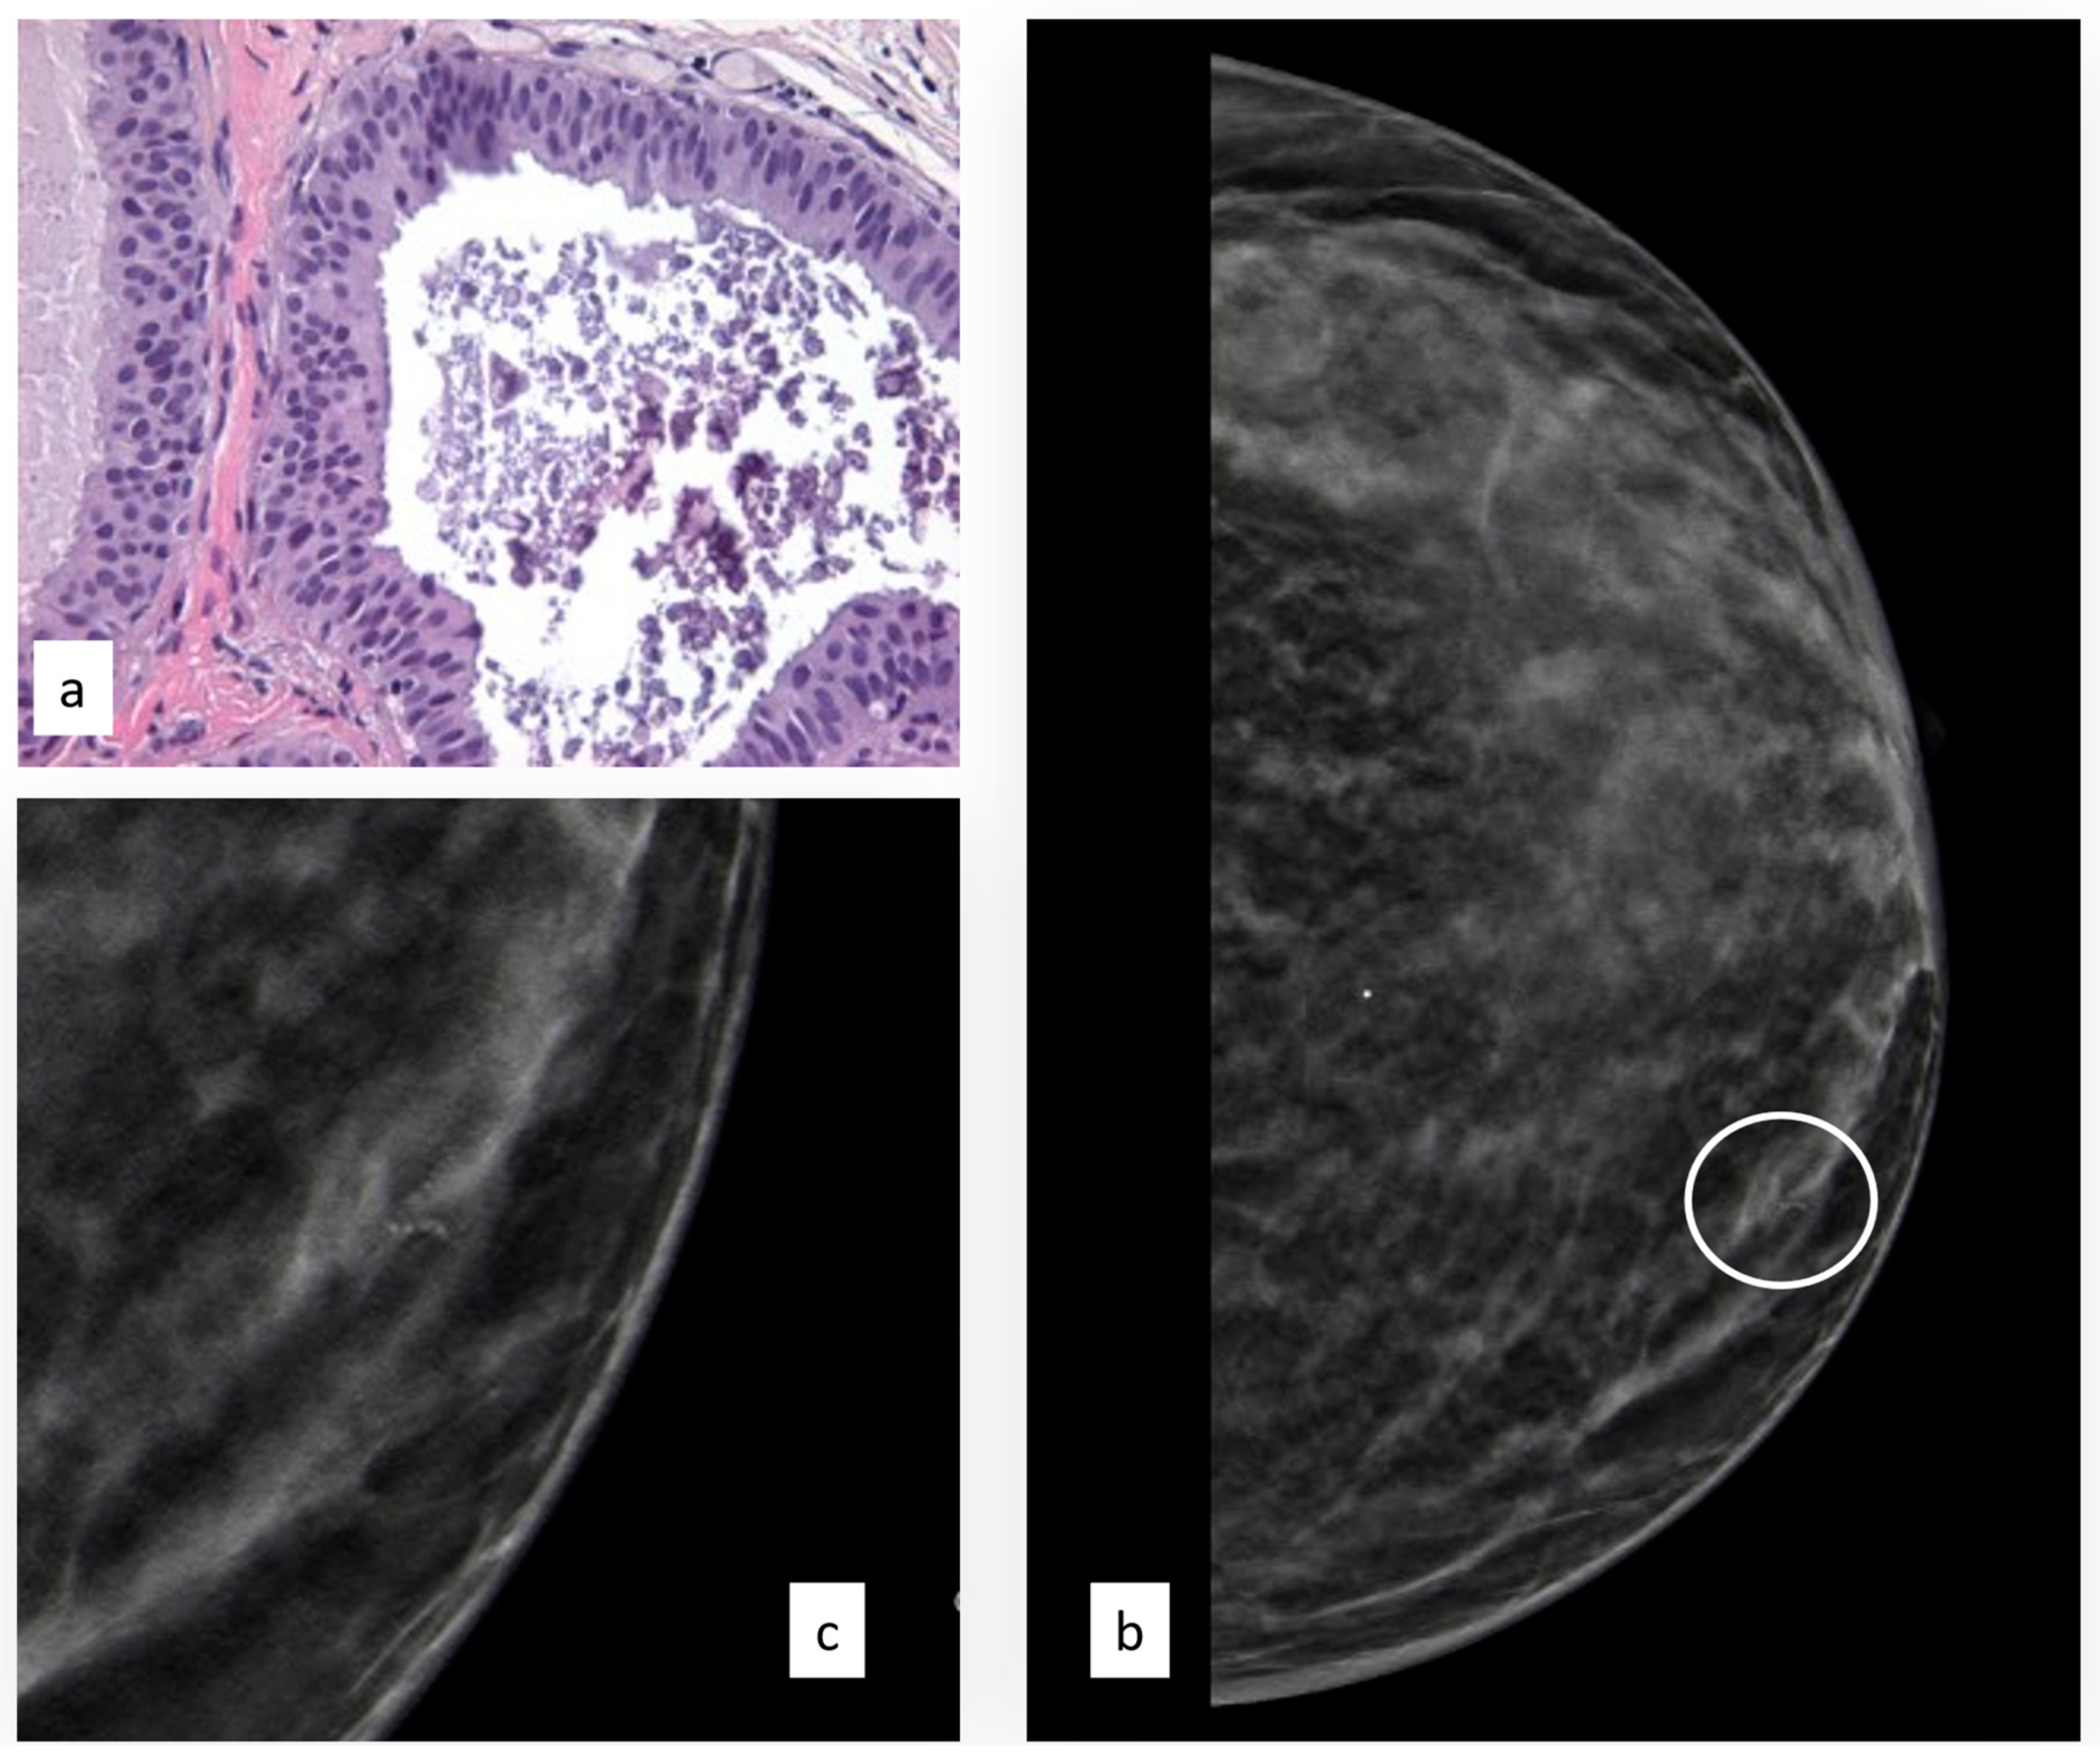

3.3.4. Atypical Papillary Lesion